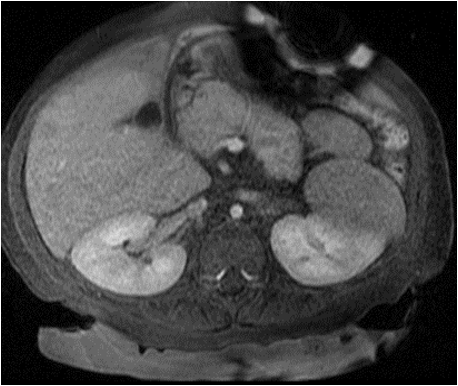

#SIOCaseSpotlight: 15-month-old with PMHx of prematurity and VACTERL was incidentally found to have a liver mass on US. AFP was 192 ng/mL (normal <8.8). MRI showed an arterially enhancing lesion in segment 6 measuring 8 mm with washout on portal venous phase.